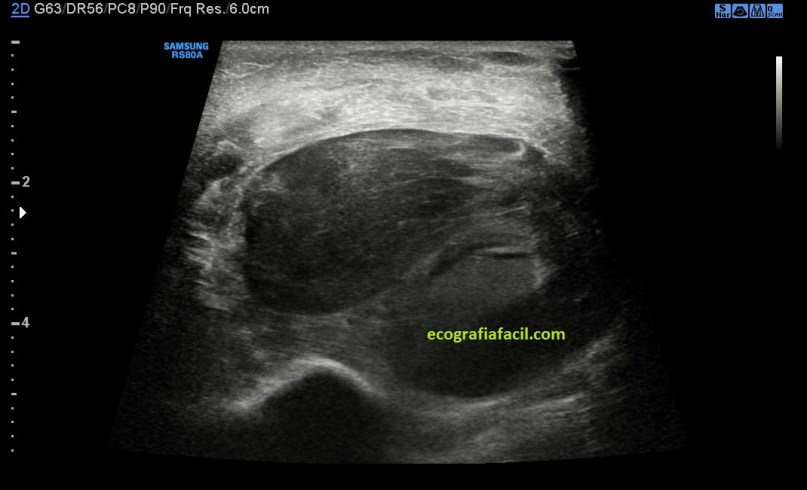

La ecografía reveló estos hallazgos:

Se objetiva una imagen heterogénea e hipoecogénica de aspecto ovalado y parece corresponder a un hematoma probablemente intramuscular. En la imagen puedes observar lo que son fibras musculares de aspecto demasiado hipoecogénicas que no son compatibles con la normalidad a ese nivel como podría ser esta imagen siguiente, mira:

Sin ser una imagen maravillosa, la 5, ejemplifica claramente lo que es el aspecto normal del tejido muscular, que no tiene nada que ver en absoluto con la semiología de las imágenes 1 a 4, intuyéndose en estas imágenes (1 a 4), tejido muscular excesivamente hipoecogénico y aumentado de tamaño, así que me gustaría que perdieses tiempo en comparar tejido muscular normal con tejido muscular afectado por un hematoma.